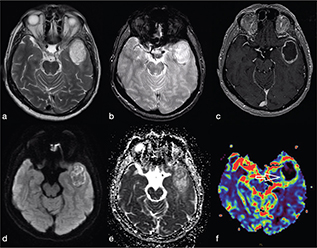

Cerebral toxoplasmosis is typical of immunocompromised patients. MRI shows multiple lesions in different stages of evolution typically located in the subcortical and periventricular white matter, in the basal ganglia and thalami. In particular, two signs are recognised as typical of toxoplasmosis: the “concentric” target sign (concentric alternating hypointense and hyperintense rims in T2w images), and the “eccentric” target sign (peripheral rim of enhancement and focal lateral eccentric enhancing nodule on T1w post-contrast) (Figure 16). On DWI, the centre of the toxoplasma abscess is seen to have ADC values higher than in pyogenic abscesses.22

FIG 16. Multiple Toxoplasma gondii Abscesses in a 45-Year-Old Immunocompromised Woman. T2w (a), T1+Gd (b, f), rCBV map (c), DWI (d) and ADC map (e). Multiple supratentorial brain abscesses in various stages of development with enhancing asymmetric nodules after Gd-injection (“eccentric target sign”) (arrows) can be observed (b, f). Note also the concentric alternating zones of hypo- and hyperintensities on T2w: “concentric target sign” (circle in a). Toxoplasma gondii abscesses typically do not show a core of restricted diffusion on DWI (asterisk in d) while low ADC values may be seen in the capsule (e).